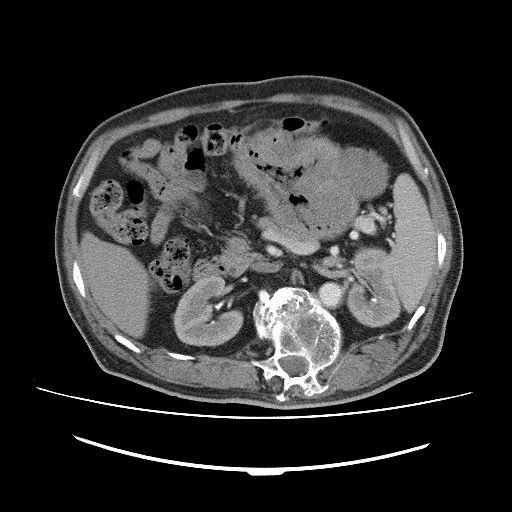

CT检查:CT扫描能够对GI无法完整显示的向腔外生长肿瘤的形态,大小清晰显示,尤其是多期增强扫描除了可以清晰的显示胃肠道管腔、管壁及肿块的形态外,还可以同时对管腔内的情况进行观察。扫描主要表现为胃肠道壁局限性增厚及软组织肿块,肿块呈圆形或分叶状,肿块大小多为4.5~8.5cm,随肿块增大,出现坏死、囊变或钙化率增高,导致密度不均匀,增强检查实性软组织成分多呈中度或明显强化,坏死囊变区无强化,肿瘤与周围组织器官界限模糊,可见存在侵袭性,如发生转移则支持恶性GIST。

CT检查特点:增强扫描肿瘤实质部分动脉期即有明显强化,静脉期持续强化,囊性部分无强化,静脉期强化可比动脉期更显著,坏死、囊变区无强化。